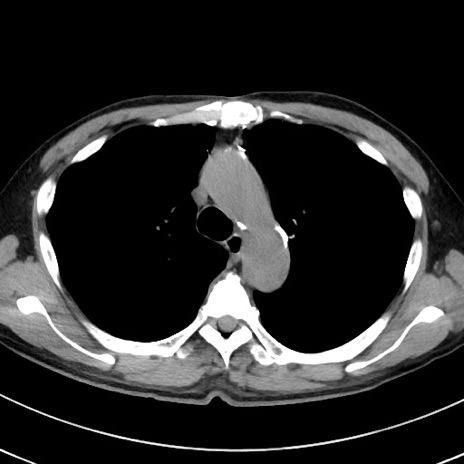

症例38(横断像)

【症例】70歳代 男性

【主訴】腹痛・嘔吐

【現病歴】昨晩より、嘔吐・腹痛あり。今朝になっても嘔吐あり。来院。

【既往歴】心臓バイパス手術、開腹胆摘、腸閉塞

【身体所見】BP 107/71mmHg、HR 116/min、腹部:平坦、軟、下腹部に軽度圧痛あり。反跳痛なし。

【データ】WBC 15100、CRP 0.32